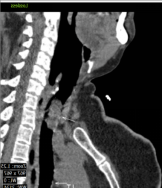

Contrast enhanced computed tomography (CECT) of neck and thorax reported intraluminal mildly enhancing polypoidal mass lesion measuring 2.58 x 1.54 x 1.51 cm (Cc X AP X Tr) in the upper trachea at the level of C6, C7 vertebral body. Significant luminal compromise was noted at the level of the mass lesion. Rest of the lung parenchyma was unremarkable. Flexible bronchoscopy examination revealed a large polyploidal growth approximately 3 cm from the vocal cords. The growth was moving with respiration and causing critical airway narrowing at the upper trachea (approximately 80%).

CECT at presentation: Intraluminal mass lesion in the upper trachea